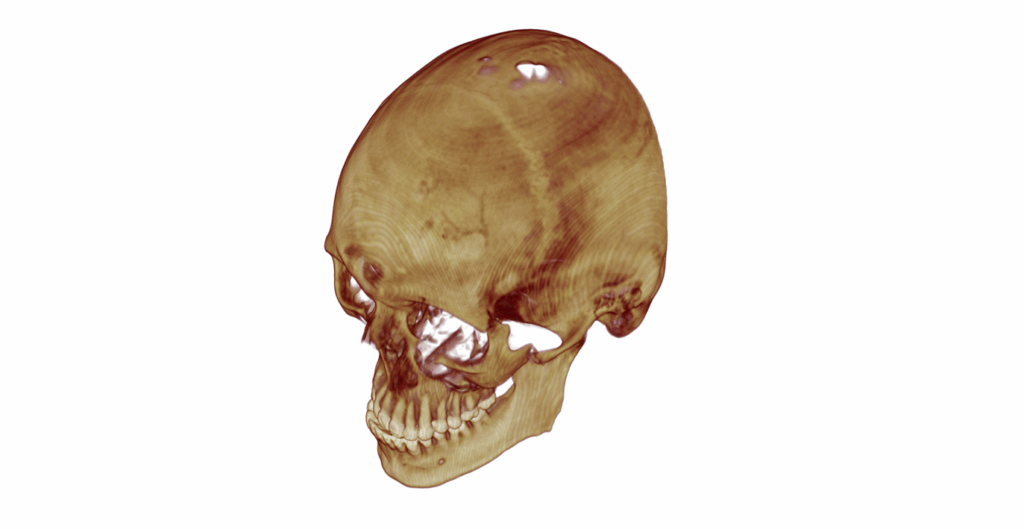

A tomografia computadorizada é o exame de escolha para avaliar o trauma em face para um diagnóstico assertivo, um bom planejamento cirúrgico e uma boa execução do tratamento.

Atualmente, com os exames de imagens tridimensionais é possível realizar planejamentos cirúrgicos virtual desde a mais simples fratura até casos extremamente complexos.